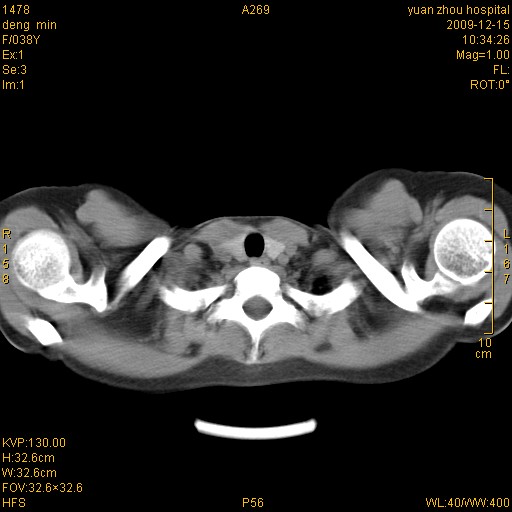

标题: CT23919:F38Y 咳嗽月余 [打印本页]

标题: CT23919:F38Y 咳嗽月余

右肺中下叶、左肺上叶舌段及左肺下叶支气管扩张合并感染。